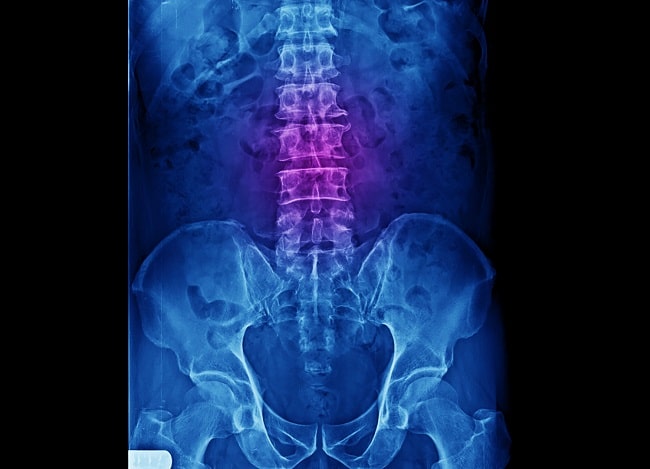

Foto Polos Lumbal

Pemeriksaan yang paling umum dilakukan pada pasien LBP adalah foto polos lumbal, pada posisi anteroposterior (AP), lateral, oblik, serta posisi lateral dengan fleksi dan ekstensi lumbal. Dari foto polos, dapat ditentukan kesegarisan tulang belakang, pergeseran korpus vertebra, kualitas tulang, ada tidaknya fraktur, jarak antara korpus vertebra (celah diskus), sklerosis endplate vertebra, penyempitan foramen vertebra, terbentuknya spur, osteofit, dan perbesaran sendi facet.[2-4]